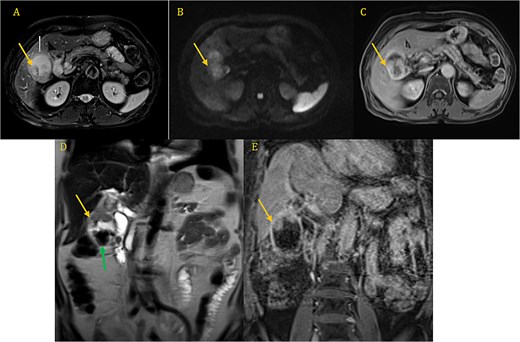

Both the computed tomography (CT) scan of the abdomen and pelvis and the magnetic resonance imaging (MRI) revealed cholelithiasis and irregular thickening of the GB wall (Fig. 1A–E).

CP-MRI demonstrates markedly dilated gallbladder with cholelithiasis (green arrow) and wall thickening involving the superior portion and the infindubulum (yellow arrow) in iso-signal on T2 (A, D), restrictive on DWI (B), with a late enhacement after injection (C, E).